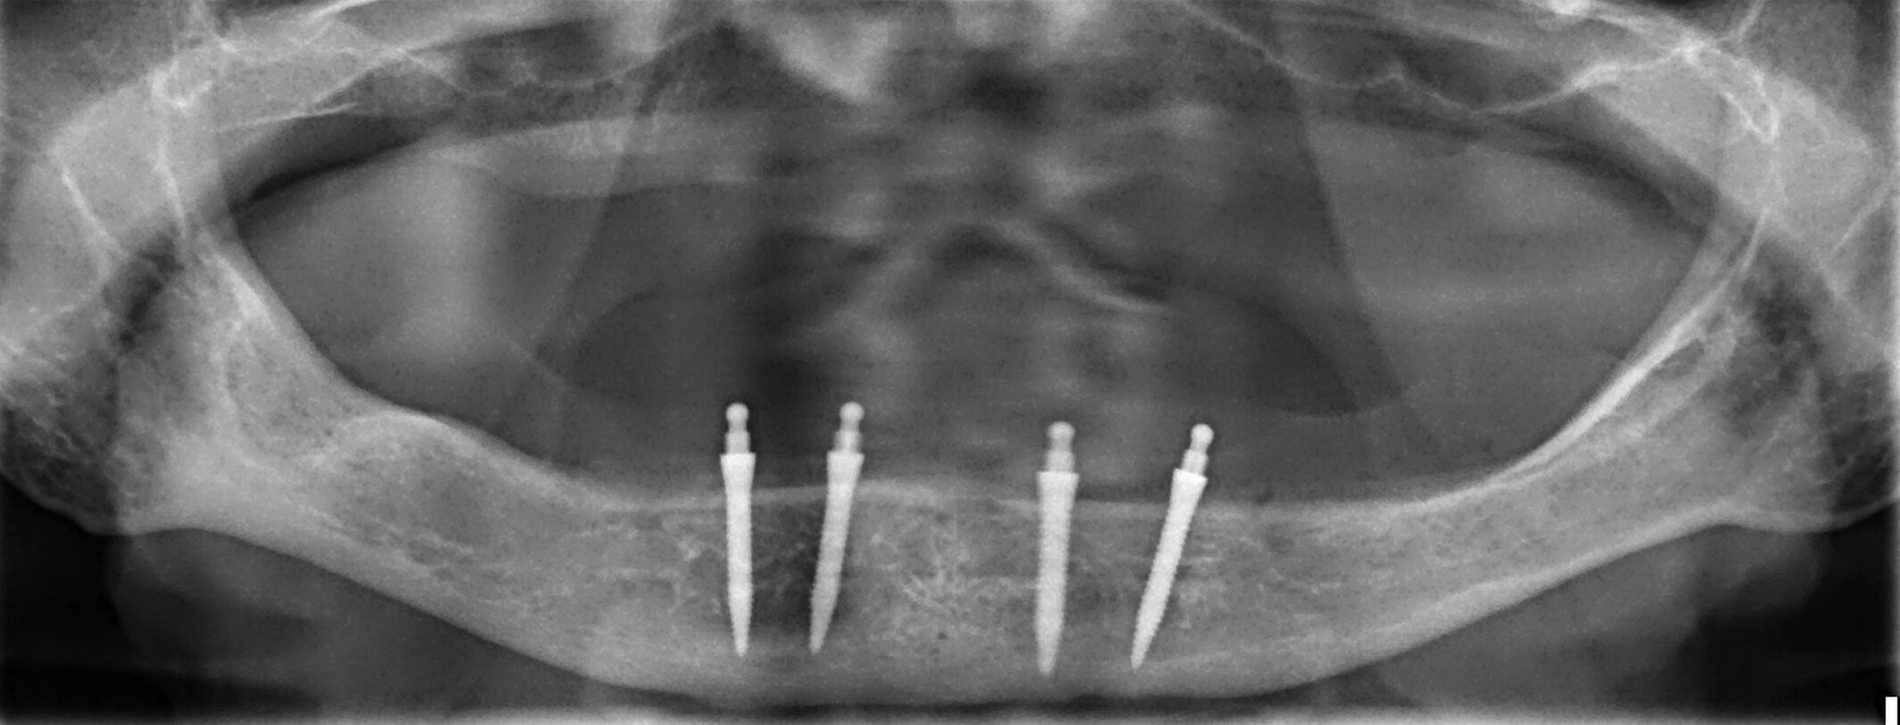

Zur Prothesenstabilisierung werden seit Ende der 1990er-Jahre Miniimplantate mit einem Durchmesser von weniger als 3 mm verwendet. Empfohlen werden hierfür vier interforaminale Implantate im Unterkiefer und sechs Implantate zwischen den Sinus maxillares im Oberkiefer (Abbildung 4) [Lemos et al., 2017]. In der Regel liegt der Implantat-Durchmesser zwischen 1,8 und 2,5 mm [Schiegnitz und Al-Nawas, 2018]. Sie sind deshalb bis auf wenige Ausnahmen [Morneburg und Proschel, 2008] einteilig [Jawad und Clarke, 2019]. Eine vollkommen belastungsfreie Einheilung ist deshalb nicht möglich [Mundt et al., 2015]. Sie eignen sich für sehr schmale Kieferkämme, bei denen anderenfalls Augmentationen notwendig gewesen wären. Viele Anwender inserieren Miniimplantate erfolgreich transgingival („flapless“) [Marcello-Machado et al., 2018]. Der Autor dieses Beitrags empfiehlt jedoch sicherheitshalber die Bildung eines kleinen Mukoperiostlappens zur Kontrolle der Insertionsstelle („mini-flap“) und die transgingivale Insertion nur bei breiten Kieferkämmen oder nach dreidimensionaler Bildgebung zusammen mit einer Bohrschablone für eine geführte Aufbereitung.

Mittlerweile gibt es zahlreiche Hersteller, die Miniimplantate in ihr Produktportfolio aufgenommen haben. Am häufigsten werden Kugelköpfe zur Verankerung auf Miniimplantaten genutzt [Marcello-Machado et al., 2018], aber es gibt dafür auch eine Reihe anderer Patrizen- und Matrizenformen wie Magnete, Locatoren oder ähnliche Verankerungen und sogar Stege [Leles et al., 2022; Lemos et al., 2017]. Beispielhaft zeigt die Abbildung 5 eines der ersten Miniimplantat-Systeme, dass inzwischen in zahlreichen Studien überprüft wurde [Enkling et al., 2019, Lemos et al., 2017, Shatkin und Petrotto, 2012]. Die Länge beginnt bei 10 mm, hauptsächlich werden jedoch 13 mm lange, 1,8-mm-Miniimplantate im Unterkiefer und 2,4-mm-Miniimplantate im Oberkiefer verwendet. Die Aufbereitungstiefe mit dem dünneren 1,1-mm-Bohrer richtet sich nach der Knochenqualität. Durch das selbstschneidende Gewinde erlangt das Implantat ähnlich einer Holzschraube seine primäre Stabilität. Erst bei einem finalen Eindrehmoment ab 35 Ncm aller Implantate pro Kiefer sollte eine Sofortbelastung erfolgen. Dafür werden die Matrizen (Housing mit einem O-Ring aus Nitrilgummi) entweder intraoral oder über eine Abformung in die Prothese einpolymerisiert. Ist das Eindrehmoment geringer, sollte die Prothese zunächst für drei Monate weichbleibend unterfüttert werden [Mundt et al., 2015]. Die Kugel nutzt seitlich nicht ab, da der O-Ring bei der Protheseneingliederung über den Äquator gleitet und darunter auf dem Insertionsvierkant verbleibt. Die Haftkraft ändert sich auch nach Jahren nicht, wenn der O-Ring bei Abnutzung ausgetauscht wird [Abou-Ayash et al., 2019].

Die kurz- und mittelfristigen Überlebensraten sofortbelasteter Miniimplantate im zahnlosen Unterkiefer entsprechen mit 92 bis 100 Prozent nach bis zu fünf Jahren den Daten von konventionellen Implantaten [Jawad und Clarke, 2019; Lemos et al., 2017]. Im direkten Vergleich waren vier Miniimplantate entweder ebenbürtig [Zygogiannis et al., 2018] oder zwei Standard-Implantaten zur Stabilisierung von Unterkieferprothesen hinsichtlich patientenimmanenter Faktoren wie Zufriedenheit mit der Versorgung und der erzielten Verbesserung der Lebensqualität überlegen [de Souza et al., 2015; Persic et al., 2016]. In einem randomisierten Vergleich gingen jedoch signifikant mehr Miniimplantate als konventionelle Implantate verloren [de Souza et al., 2015]. In dieser Studie waren alle Implantate 10 mm lang. Der Trend von mehr Verlusten von Miniimplantaten mit einer Länge von < 12 mm wird in anderen Studien bestätigt [Mundt et al., 2014; Van Doorne et al., 2020]. Die minimalinvasive und relativ schnelle Insertion von Miniimplantaten führt zu weniger postoperativen Beschwerden und Schwellungen als bei konventionellen Implantaten mit Bildung eines Mukoperiostlappens und mehreren Schritten bei der Implantatbettaufbereitung [Kovacic et al., 2018]. In der Universitätszahnklinik Rostock wurden Planung, Insertion und prothetische Versorgung von Miniimplantaten im zahnlosen Unterkiefer von zwanzig 56- bis 87-jährigen Patienten sogar erfolgreich durch Studenten unter Anleitung im klinischen Kurs erbracht [Kämmerer et al., 2021].